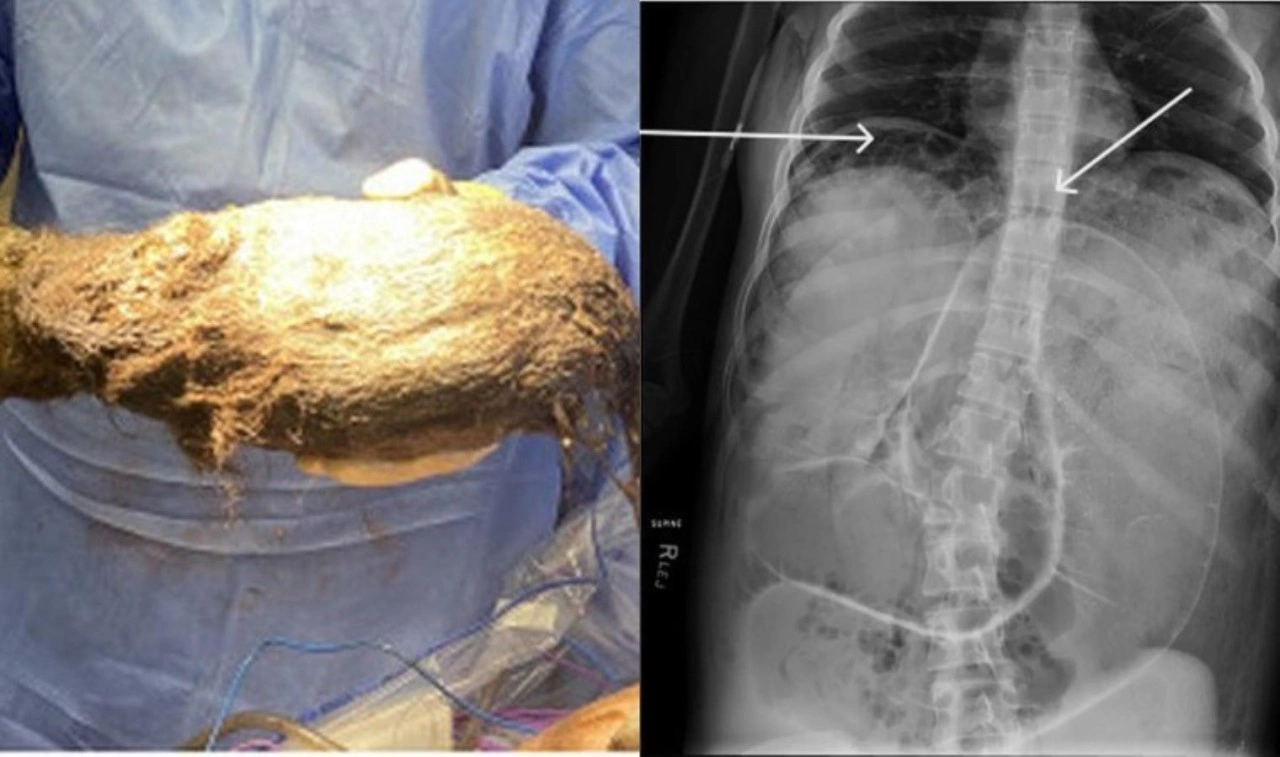

Karmaşık bir prosedürün ardından doktorlar, kızın midesinden 2,468 gram ağırlığında bir kıl yumağı çıkardılar.

Kıl yumağının, laparotomi olarak bilinen bir işlemle cerrahi olarak çıkarılması gerekiyordu, ancak prosedür kızın sağlığının hızla kötüleşmesine neden oldu ve hipotermi durumuna girerek kanın pıhtılaşmasını zorlaştıran bir durum olan koagülopati belirtileri gösterdi.

Gerçekleştirilen operasyon sonrasında kıl yumağı alındı, kızın durumunun iyi olduğu belirtildi.